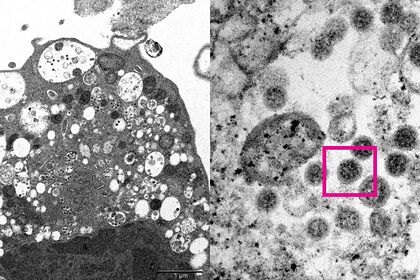

Отмечается, что исследователям впервые удалось сделать электронную микрофотографию клетки (Vero E6) почки обезьяны, которая была инфицирована Омикроном.

На снимке видны повреждения с набухшими везикулами, в которых содержатся вирусные частицы. Также ученым удалось разглядеть скопления характерных сферообразных объектов с шипами в форме короны на их поверхности.